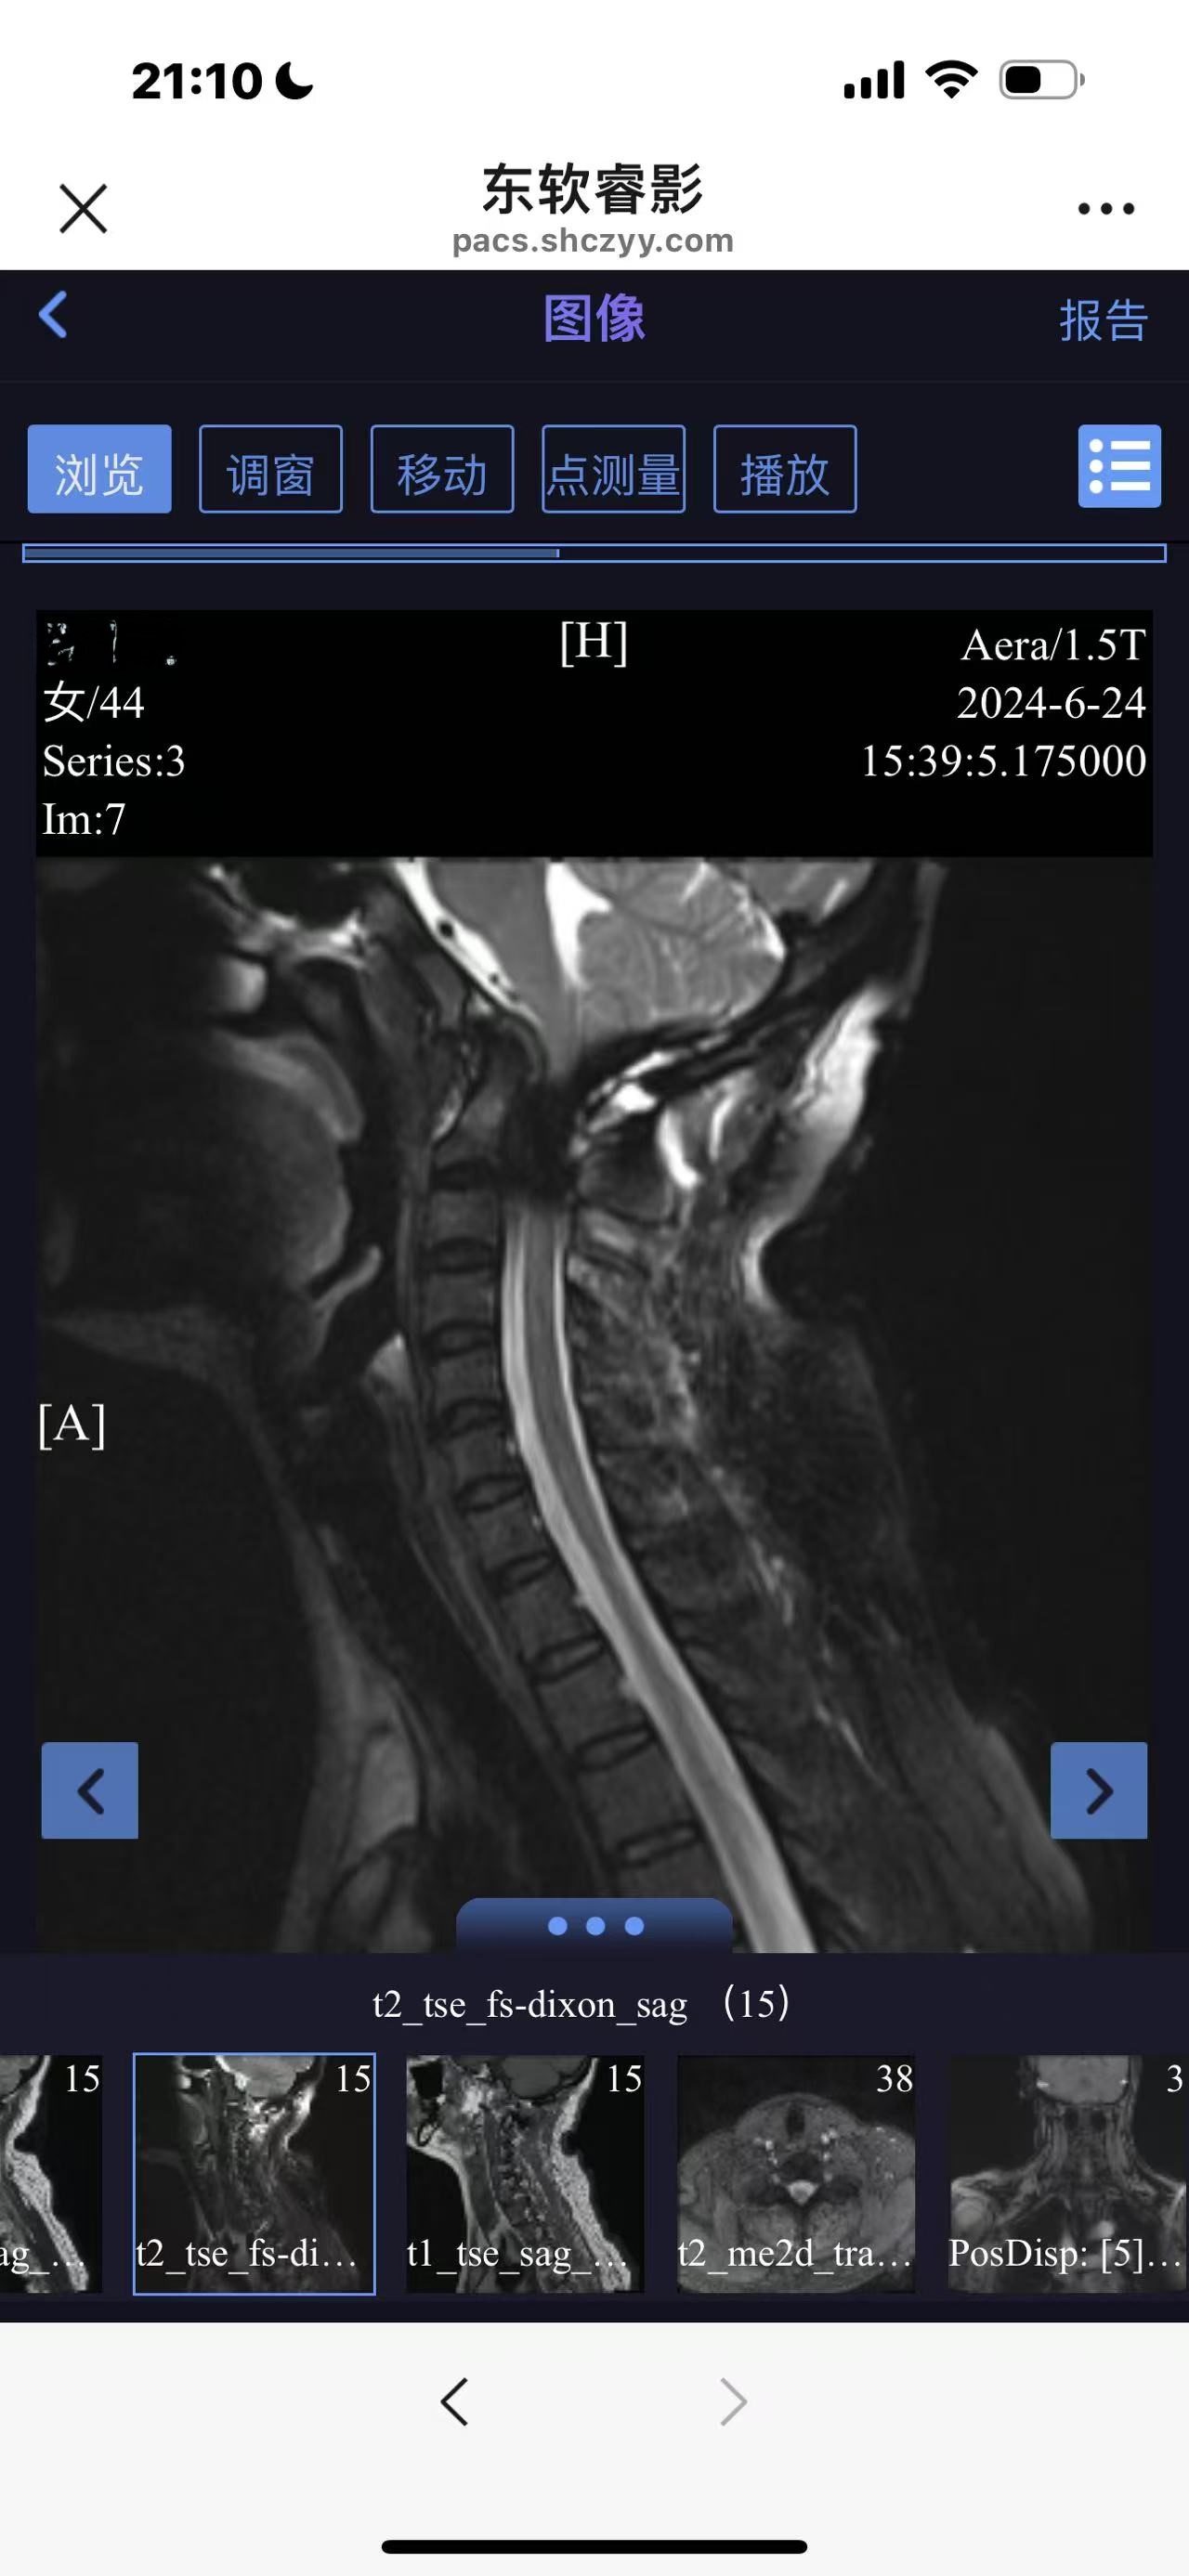

• 诊断:寰枢椎脱位

• 日期:2024.06

• 医院:上海长征医院

• 术后状况:没有复位

• 术后影像: